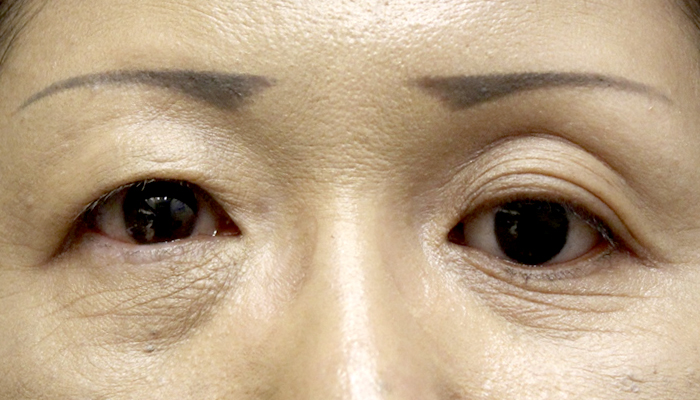

症例2

| 術前 | 左義眼、眼球陥凹 |

|---|---|

| 術後 | 左義眼台包埋、左眼窩内ヒアルロン酸注入後 |

| 治療費 | 準備中 |

| 治療のリスク | 腫れが引かない、内出血がある、目が閉じにくい、完全に閉じないなどのリスクがあります |